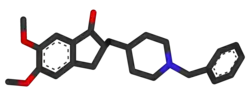

| Medicação | Inibidores da acetilcolinesterase, antagonistas dos recetores de NMDA (poucos benefícios)[6] |

Atualmente são usados cinco medicamentos no tratamento dos problemas cognitivos de Alzheimer: quatro são inibidores da acetilcolinesterase (tacrina, rivastigmina, galantamina e donepezila), sendo o outro um antagonista dos recetores de NMDA (memantina).[169] No entanto, os benefícios da sua utilização são pouco significativos.[170][171]

A diminuição da atividade dos neurónios colinérgicos é uma característica bem compreendida da doença de Alzheimer.[172] Os inibidores da acetilcolinesterase são usados para reduzir a velocidade a que a acetilcolina (ACh) é fragmentada, aumentando assim a concentração de ACh no cérebro e combatendo a perda de ACh provocada pela morte dos neurónios colinérgicos.[173] Existem evidências da eficácia destes medicamentos em casos leves a moderados da doença,[174][175] e algumas evidências durante a fase avançada. Só a donepezila é que está aprovada para o tratamento da demência avançada de Alzheimer.[176] A utilização destes fármacos no défice cognitivo ligeiro não demonstrou ter qualquer efeito no atraso do aparecimento de Alzheimer.[177] As reações adversas mais comuns são náuseas e vómitos, ambos ligados ao excesso colinérgico. Estas reações adversas manifestam-se em cerca de 10-20% dos utilizadores, a sua gravidade é entre leve e moderada e podem ser controladas através do ajuste gradual das doses de medicação.[178] Entre os efeitos secundários menos comuns estão cãibras musculares, diminuição do ritmo cardíaco, diminuição do apetite e do peso e aumento da produção de ácido gástrico.[179]

O glutamato é um neurotransmissor excitatório do sistema nervoso, embora uma quantidade excessiva no cérebro possa provocar a morte das células através de um processo denominado excitotoxicidade, o qual consiste na sobre-estimulação dos recetores de glutamato. A excitotoxicidade ocorre não só na doença de Alzheimer, como também noutras doenças neurológicas como na doença de Parkinson e na esclerose múltipla.[180] A memantina é um antagonista dos recetores de NMDA não competitivo, inicialmente usado no tratamento de gripe. Atua no sistema glutamatérgico bloqueando os recetores NMDA e inibindo a a sobre-estimulação pelo glutamato.[180] A memantina é moderadamente eficaz no tratamento de Alzheimer moderada a grave. No entanto, os seus efeitos nas fases iniciais da doença são ainda desconhecidos.[181] As reações adversas com memantina são pouco frequentes e leves, incluindo alucinações, confusão, tonturas, dores de cabeça e fadiga.[182] A combinação de memantina e donepezila tem demonstrado ser estatisticamente significante, mas de eficácia clínica marginal.[183]